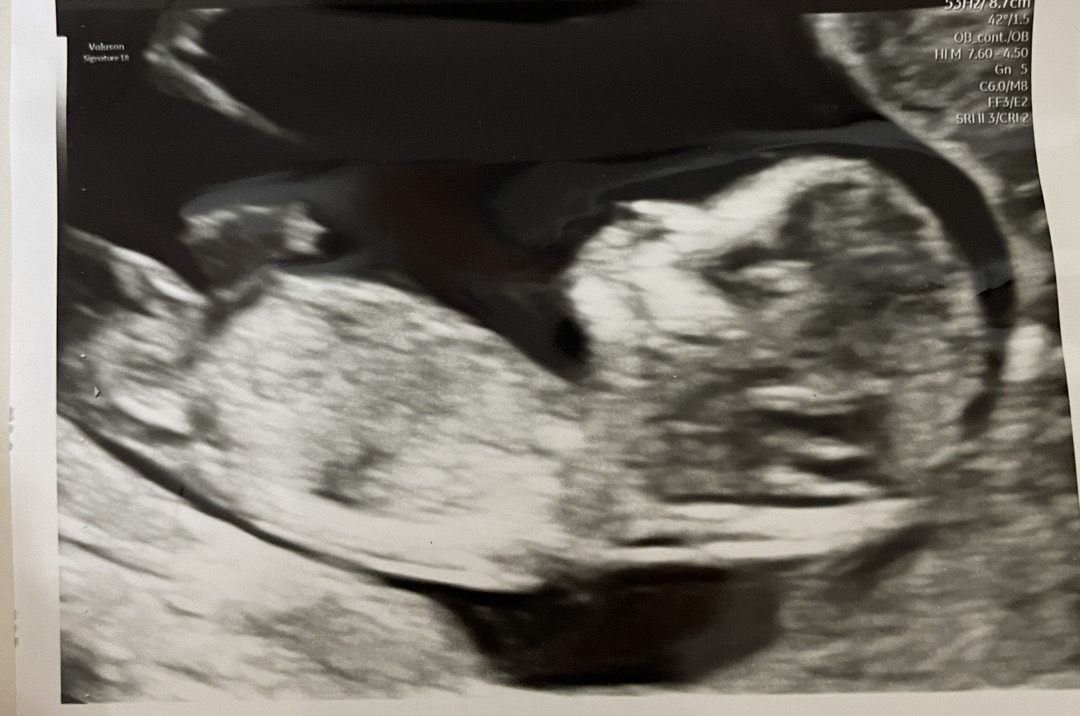

11주 각도법..!!

11주 2일차 병원갔는데, 아기가 12주 1일차 크기여서 각도법 볼수있는 시기라해서요ㅎㅎㅎ 각도법 고수님들 성별 봐주세요!!

아들같은데 반전될수도요